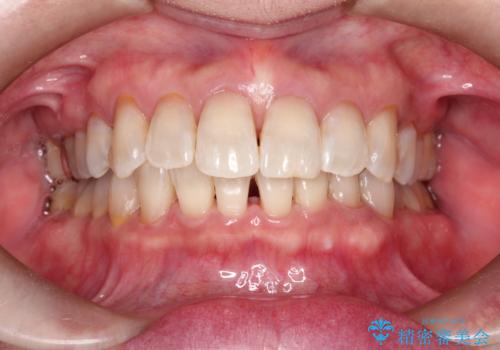

PMTCでステイン除去をし綺麗な歯へ

- 久々のクリーニングで来院されました。歯の表面のステイン付着と、下顎前歯に歯石がみられました。今回はPMTCをおすすめしました。

ステインを除去したことで全体のトーンが明るくなりました。下顎前歯は歯石で埋まってしまっていたため、クリーニング後はスペースができたように見えますが、歯本来の形へ戻りました。